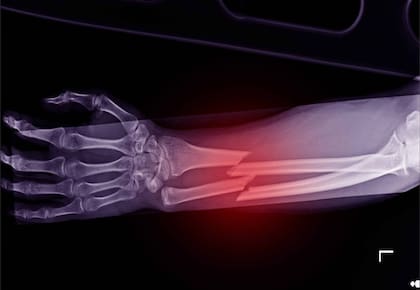

Profesionales de la salud indagaron sobre una cuestión que, hasta el día de hoy, no tenía explicación: ¿Existen personas que son más propensas a sufrir quebraduras en sus huesos? Informes de osteópatas, kinesiólogos y otras profesiones afines indicaron que existen tres teorías que pueden aclarar el panorama.

El doctor Suhail Hussain dio tres variantes a tener en cuenta para entender por qué ciertas personas pueden vivir con un yeso o una bota ortopédica y otros, en cambio, jamás tuvieron un raspón o no conocen, siquiera, lo que es esperar en la guardia de un hospital.